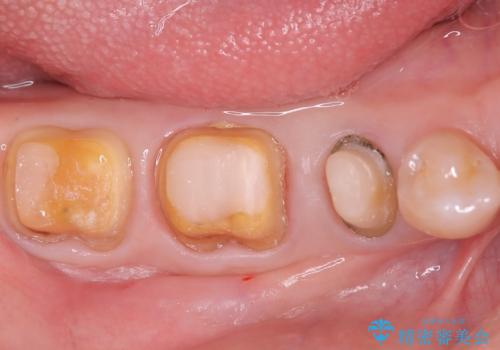

- 「銀歯が目立つのがずっと気になっていた」とのご相談で来院されました。左下の奥歯(5・6・7番)には保険治療で入れた銀色の被せ物が入っており、笑ったときや口を開けた際に見えるのが気になるとのことでした。

まずは銀歯を慎重に取り外し、歯の状態を確認しました。虫歯や劣化した部分は丁寧に除去し、必要に応じて土台を整えたうえで、セラミッククラウンを作製する準備を行いました。色や形は周囲の歯になじむように細かく調整し、自然な透明感やツヤを再現しました。